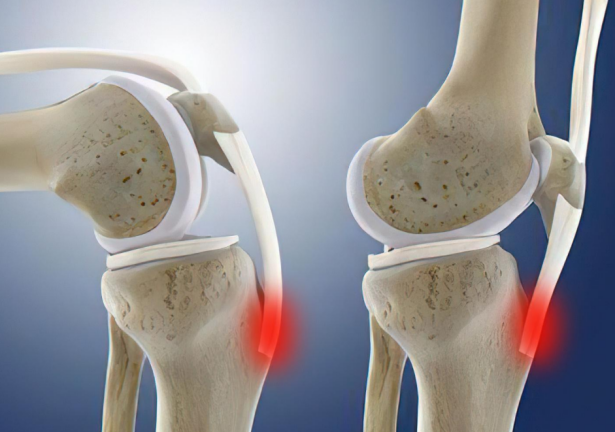

从解剖角度看,儿童的胫骨近端骨骺为软骨,前缘呈舌状下缘,称为舌状骨骺。该处的骨化中心在11岁左右出现,约16岁左右骨化中心才与胫骨近端骨骺融合成为胫骨结节。在成为胫骨结节处,该处较薄弱,而且骨骺正处于髌韧带的止点,剧烈运动下,股四头肌的强烈或长期持续牵拉容易导致髌韧带出现过度牵拉损伤,导致舌状下缘的骨骺出现损伤、撕脱。进而影响该处的血液循环,引起骨质增生,导致胫骨结节增大,明显向前突出。不少成年人胫骨结节突出明显,就是由于此病引起。

该病的主要症状为髌骨下方、胫骨近端前方疼痛、胫骨结节肿胀和局部压痛,跑跳运动后加重,上楼梯、斜坡及屈膝、下蹲时疼痛明显。